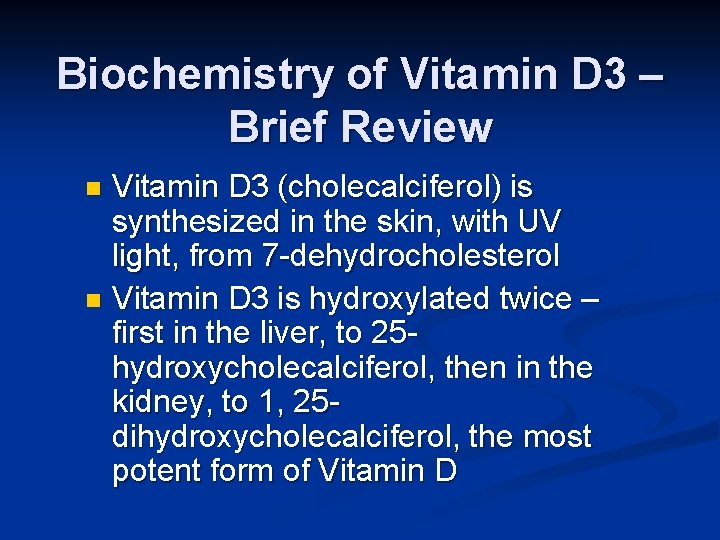

Biochemistry of Vitamin D 3 – Brief Review Vitamin D 3 (cholecalciferol) is synthesized in the skin, with UV light, from 7 -dehydrocholesterol n Vitamin D 3 is hydroxylated twice – first in the liver, to 25 hydroxycholecalciferol, then in the kidney, to 1, 25 dihydroxycholecalciferol, the most potent form of Vitamin D n